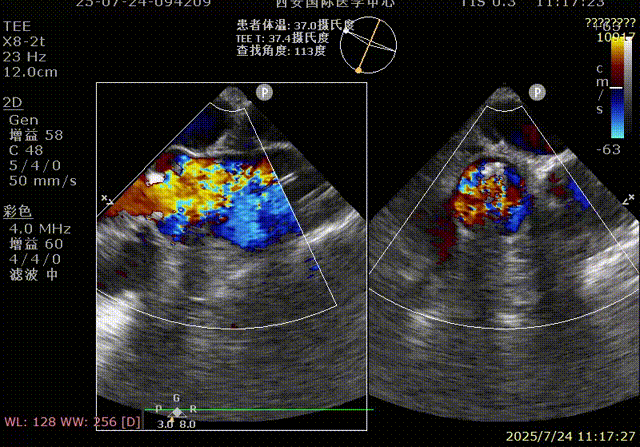

术前超声

术后超声